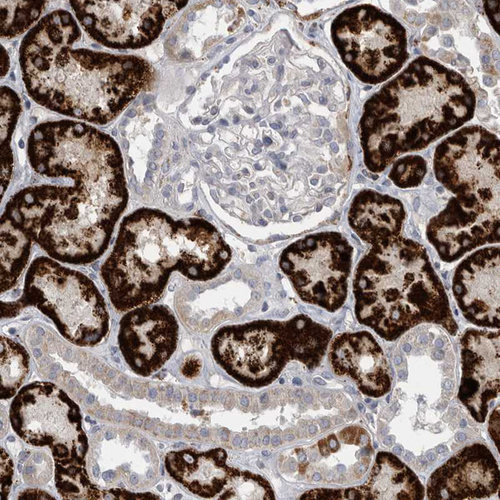

Immunohistochemistry analysis in human kidney and skeletal muscle tissues using HPA026077 antibody. Corresponding GATM RNA-seq data are presented for the same tissues.